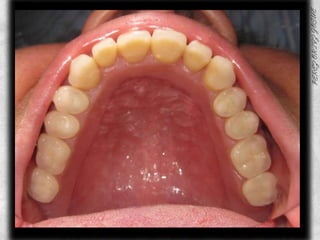

ARCADA SUPERIOR CLASIFICACIÓN DE OSAWA TIPO IFORMA DE PROCESO “U”LINEA MEDIA COINCIDE CON EL RAFE PALATINOCOLOR ROJO BRILLANTETEXTURA LISAPROCESO ALVEOLAR TIPO IAPARENTEMENTE SIN PRESENCIA DE CANDIDABUENA INSERCION DE LOS FRENILLOS